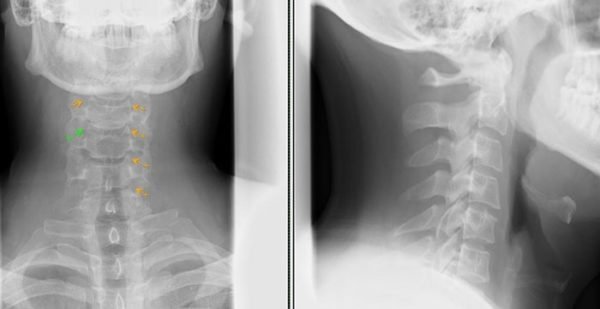

Исследование брюшной полости с использованием рентгеновского излучения может быть проведено в двух вариантах: обзорной рентгенографии и процедуре с применением контрастного вещества. Для выявления патологий в легких широко используется метод рентгеноскопии. Рентгенологическое обследование позвоночника, суставов и других частей скелета является очень востребованным методом диагностики.

Для неврологов, травматологов и ортопедов важно использовать данный метод обследования, чтобы точно определить состояние своих пациентов. Рентгеновское исследование позволяет выявить грыжу позвоночника, сколиоз, различные микротравмы, нарушения костно-связочного аппарата (патологии здоровой стопы), переломы (лучезапястного сустава) и многое другое.